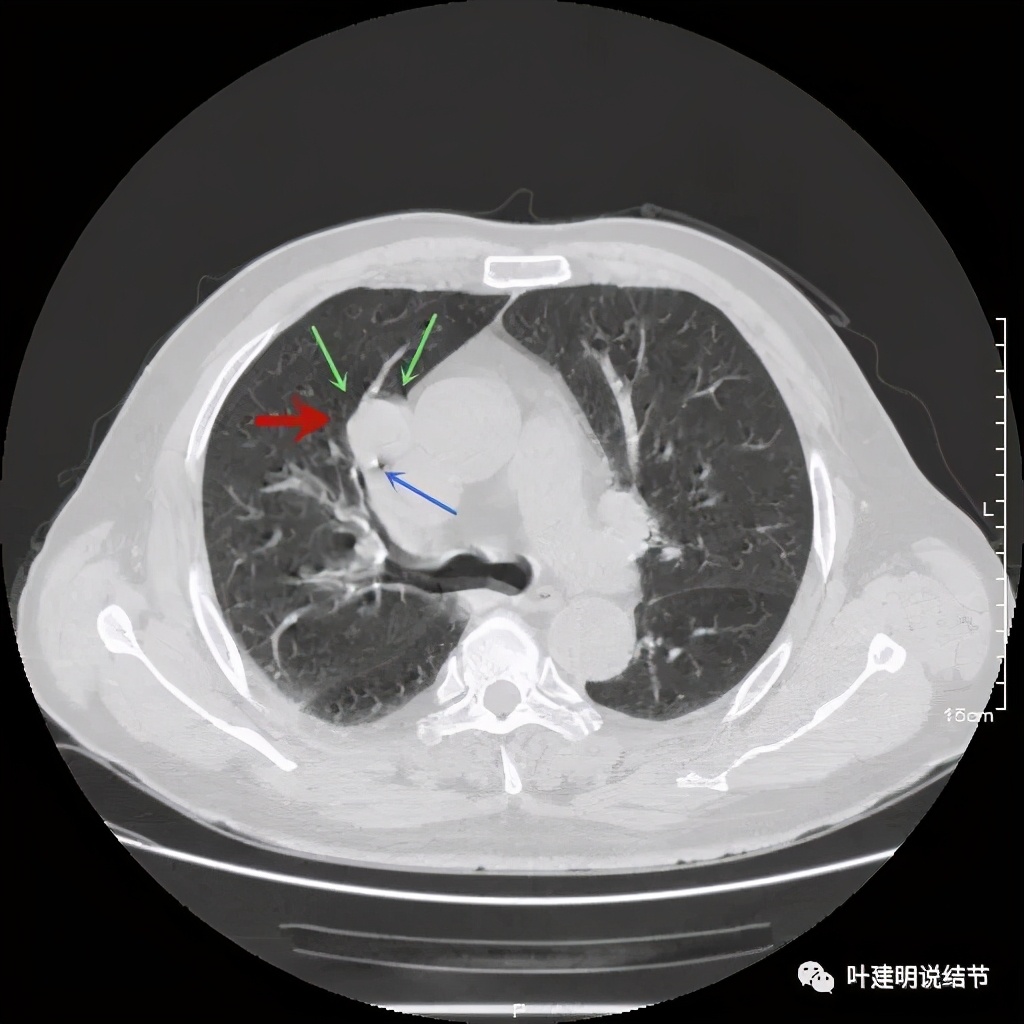

可见右上叶占位,我们现在知道了结果以后回头看,发现病灶的边缘在各个层面都是过于光滑(绿色箭头所示)。血管紧贴病灶边走行(桔色箭头所指),是不是有侵犯看不清楚,若是靶扫描加重建可能会更清楚点。支气管感觉也是贴着病灶走,但有的层面是不是截断,也不看的不太清楚。有的层面见局部有点状高密度(蓝色箭头所指),是不是错构瘤的局部钙化呢?若是纵隔窗又是如何?

上图示病灶

上图示病灶密度不均

上图示病灶局部点状高密度(蓝色);边缘过于光滑(绿色)